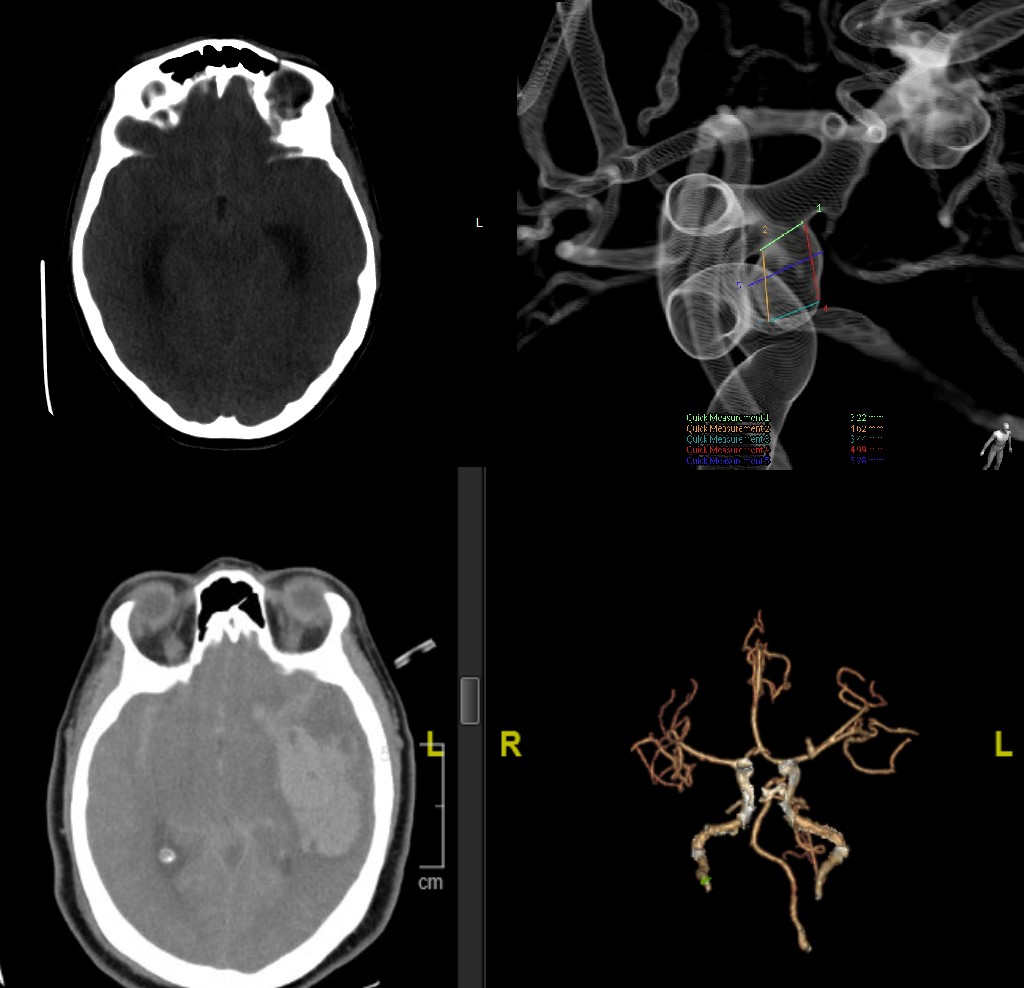

Severe daily head & neck aches in teenager resolved after restoring sagittal alignment with three 6mm CoCr rods & many posterior osteotomies. Thanks to co-surgeon Dr. Tiffany Perry #Spine #Orthopaedics #Neurosurgery #orthotwitter Cedars-Sinai